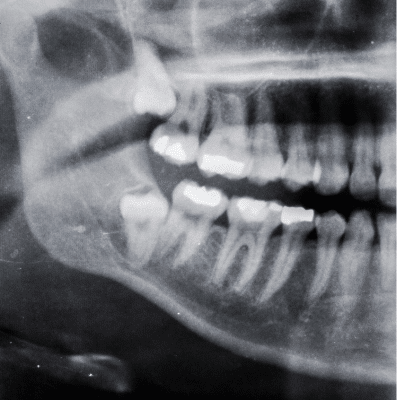

Impaction commonly affects the third molars, also known as wisdom teeth, but can also occur with other teeth, such as canines and premolars. Several factors can contribute to tooth impaction, including:

- Lack of Space: Insufficient space in the jaw can prevent a tooth from erupting properly.

- Overcrowding: Crowded teeth or irregular positioning can obstruct the path of erupting teeth.

- Abnormal Growth: Irregular growth patterns of the jaw or teeth can predispose certain teeth to impaction.

- Damage to Adjacent Teeth: They can exert pressure on neighboring teeth, causing damage or misalignment.

- Cyst Formation: In some cases, they may develop cysts or tumors, potentially causing bone damage and other complications.